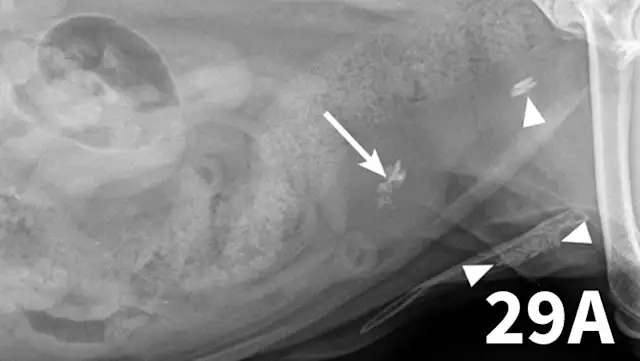

The normal urethra of dogs and cats is difficult to visualize on survey radiography and ultrasonography. Radiopaque urethroliths can be observed on survey radiographs, and therefore the entire urethra should always be included in the field of view (Figure 28). In male dogs, it is useful to pull the hindlimbs forward to assess the urethra between the pelvis and os penis (Figure 29). The prostate gland and proximal urethra, before entering the pelvic canal, can be visualized with ultrasonography, especially if there is urethral distention. In male dogs, the urethra at the proximal os penis can be evaluated with ultrasonography to assess for urethroliths, which commonly lodge in this location. Positive-contrast retrograde urethrography is the best tool for diagnosis of intraluminal, intramural, and extramural compressive urethral disorders as well urethral rupture (Figure 30).